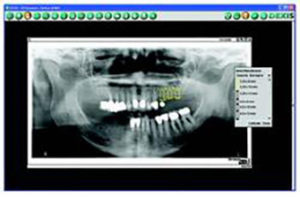

I also use my digital radiography’s implant software for my implant planning. This tool allows me to precisely calibrate my digital radiographs and select from a comprehensive library of implant models that, once placed on the image, are digitally sized accurately for 2 dimensions (Fig. 4).